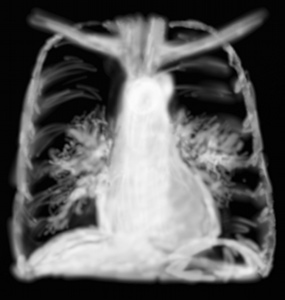

RP mucoviscidose

Les syndromes bronchiques se voient quand une maladie chronique très évoluée comme la dilatation des bronches ou bronchectasies, la mucoviscidose se compliquent d’une surinfection. Les images peuvent montrer des opacités linéaires partant des hiles et se dirigeant vers la périphérie, des images arrondies en cocardes représentant les bronches vues en coupes, ou des images en rail quand elles sont vues dans le sens de la longueur.